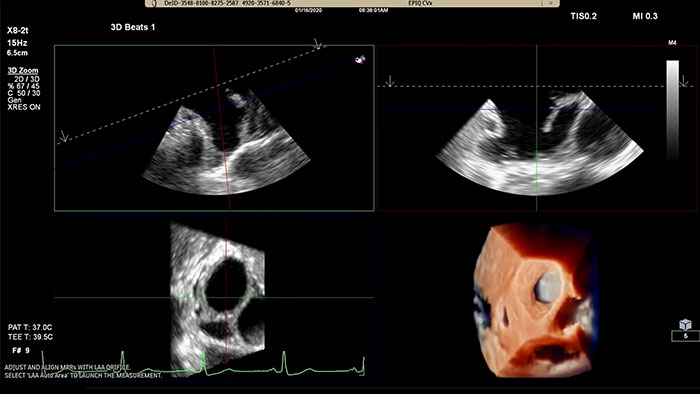

Schnelle Durchführung von Messungen am Ostium des linken Vorhofohrs in herkömmlicher Darstellung oder in TrueVue Glass Darstellung mit 3D Auto LAA